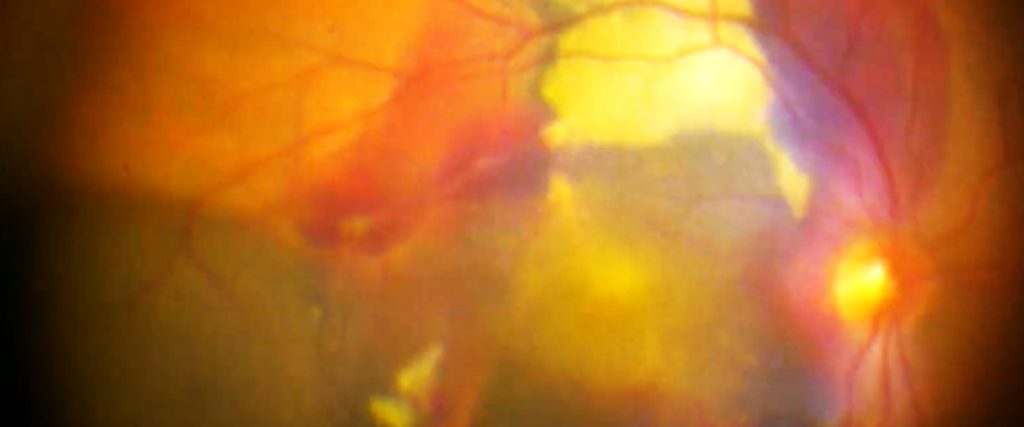

Wet AMD is less common but more severe, leading to rapid vision loss. It occurs when abnormal blood vessels grow under the retina and leak blood or fluid, causing scarring.

Sometimes the bleed under the retina in wet AMD needs to be treated surgically by injecting clot dissolving medication subretinally.